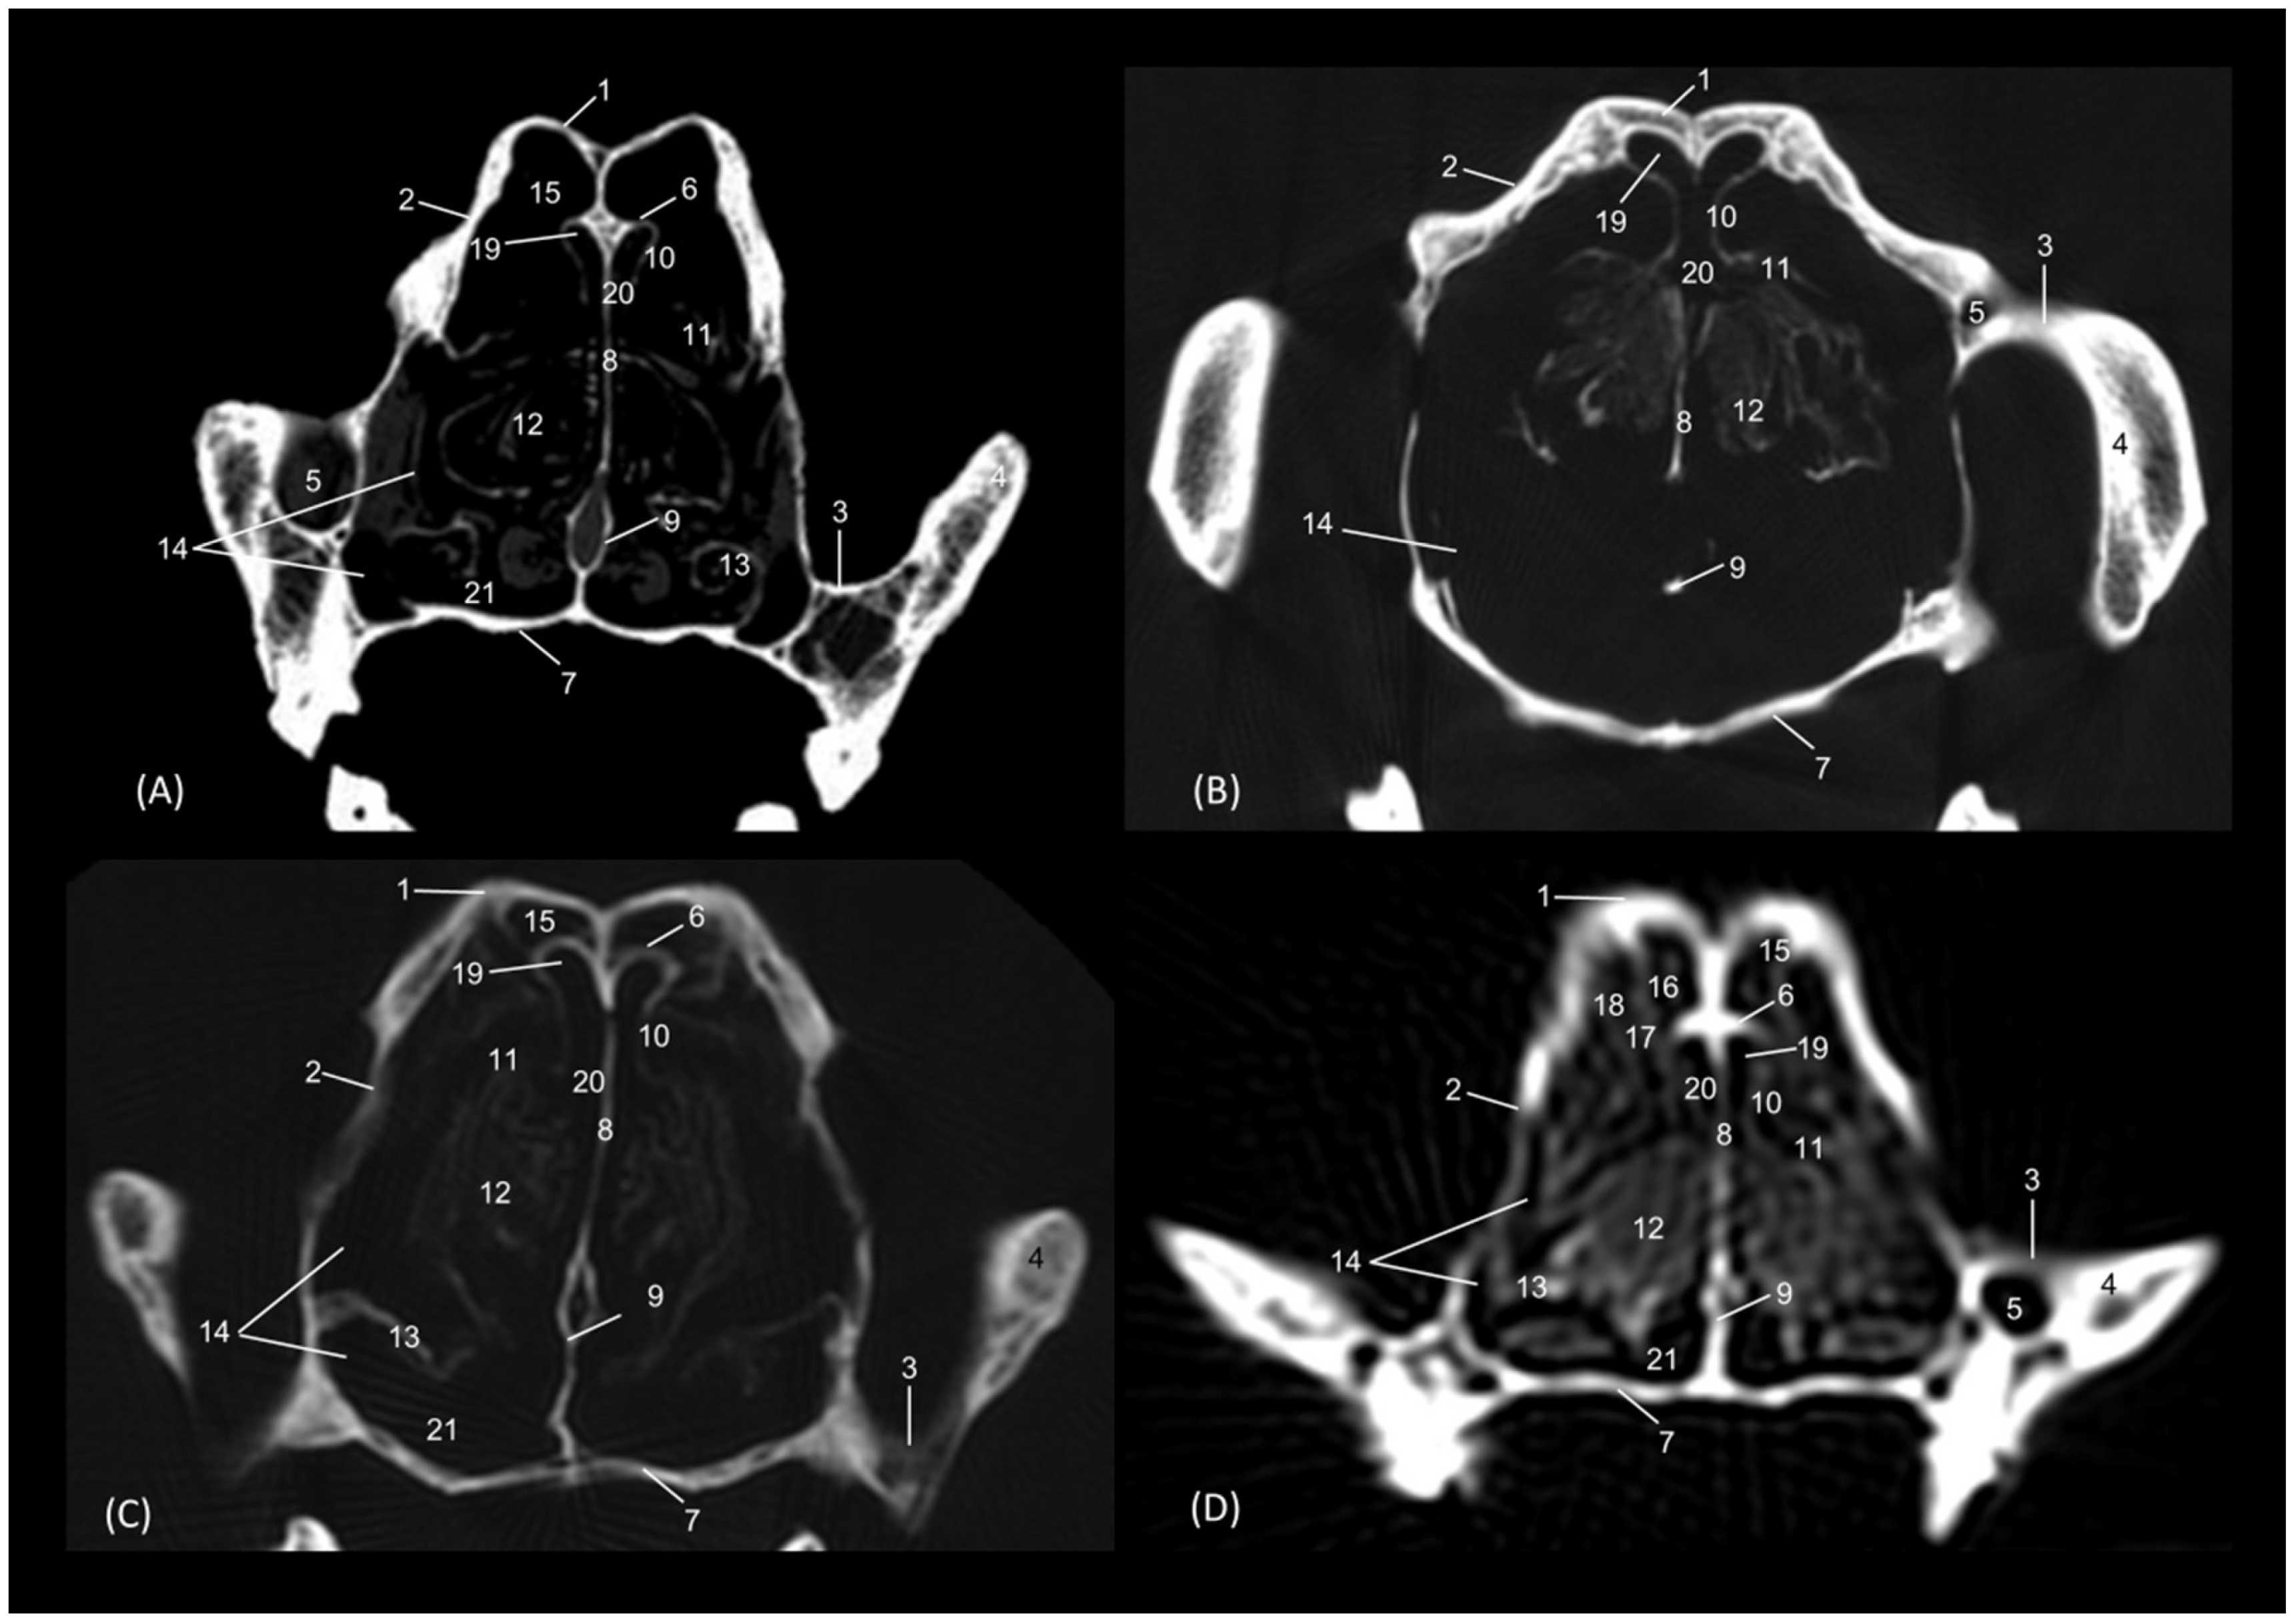

Figure 22 shows the greater thickness of the frontal bone and maxillae of the lion compared to the other species studied. At this level, the temporal process of the zygomatic bone is visible in all four species and the third endoturbinate reaches its greatest development. This was observed as a set of hyperattenuated lamellae on the medial part of the nasal cavity. The ventral nasal concha was already very small in all four species. Ectoturbinates were seen at this level only in the domestic cat. The frontal sinus was now apparent in the cheetah, but not yet in the lion. The tectorial plate of the ethmoid bone was seen as a hyperattenuated area at the base of the frontal sinus.

Figure 22. Amira representative transverse CT images at level of the middle portion of the respiratory part, level III. Images are oriented so that the left side of the head is to the right and the dorsal is at the top. All views are rostral. (A): Leopard; (B): Lion; (C): Cheetah and (D): Cat. 1. Frontal bone; 2. Maxilla; 3. Zygomatic process: body; 4. Zygomatic bone: temporal process; 5. Infraorbital canal; 6. Ethmoid bone: tectorial plate; 7. Maxilla: palatine process; 8. Nasal septum; 9. Vomer; 10. Dorsal nasal concha; 11. Middle nasal concha; 12. 3rd endoturbinate; 13. Ventral nasal concha; 14. Maxillary recess; 15. Frontal sinus; 16. 1st ectoturbinate; 17. 2nd ectoturbinate; 18. 3rd ectoturbinate; 19. Dorsal nasal meatus; 20. Common nasal meatus; 21. Ventral nasal meatus.